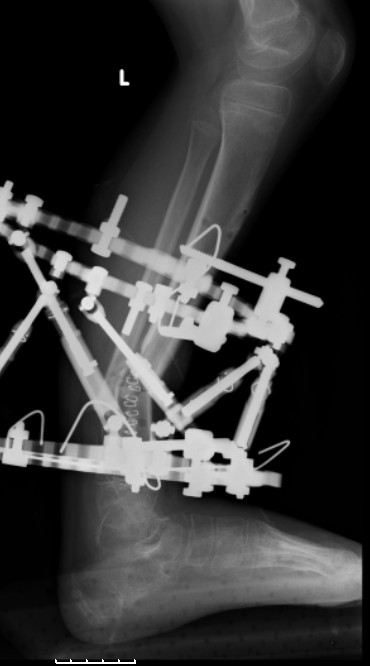

Another choice is simply perform shortening + posterior angulation with Ilizarov or TSF , than gradual correction of the angulation.After all apply third ring on the proximal tibia and start lengthening.

We had recently similar case in 14 years old boy with 45 mm bone defect after open tibial fracture.Boy doing excellent .This technique is not new, Sasha Lerner did it in Rambam , Rozbruch wrote also.

Another advantage of this techniqe is relaxation of soft tissue and possibility for closure even large defects of the skin.In your case I will apply ring on the foot and mid diaphysis of the tibia ,removal of the fibular plate,sindesmotic wire, and after correction of angulation on the proximal tibia.